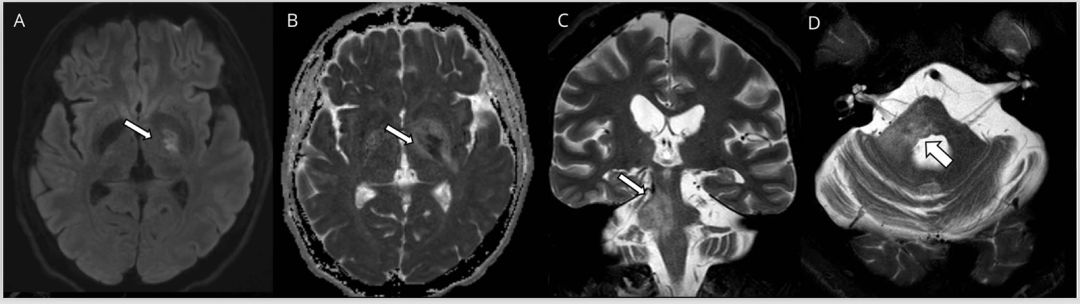

大多数NMOSD患者常可见头颅MRI异常,并且位于幕下(图2,A–E)。脑干受累似乎在AQP4-IgG血清反应阳性的NMOSD中更为常见,而延髓最常见。尽管不是完全特异性,但有些病变相对于MS更常见于NMOSD,包括与第四脑室相邻的背侧延髓的线性病灶。围绕第三脑室的间脑和中脑头端的病灶是NMOSD的特征性表现。NMOSD病灶一般呈斑片状,“云状”样增强,尤其是在脑室和胼胝体周围,而MS不会有这样的增强。弥散加权成像和表观扩散系数(ADC)在 NMOSD中均显示出与血管源性水肿一致的高信号。其他典型表现包括纵向广泛的视神经病变(> 50%长度)和有症状的、广泛性实质白质病变。

在MRI上,MOG-IgG引起的脱髓鞘更可能累及深部灰质,球后(前部)视神经和脊髓圆锥(AQP4-IgG血清阳性患者更常累及视交叉和颈髓)。脑桥病灶通常呈蓬松样外观,在MOG-IgG中比在AQP4-IgG CNS疾病中更常见(图2,D和E),而间脑和四脑室(包括背侧延髓)高信号均可见于AQP4-IgG和MOG-IgG血清反应阳性患者。极后区综合征和LETM不足以区分MOG-IgG和AQP4-IgG。MOG-IgG脱髓鞘引起的皮层病灶通常较大且伴水肿,在标准的T2 / FLAIR序列上清晰可见,与MS中的皮层病灶不同,后者通常很小,在标准的1.5T和3T MRI T2 FLAIR序列中很难观察到。大的皮层病灶非AQP4-IgG NMOSD的典型表现。

图2 NMOSD患者的MRI影像。(A-C)顽固性恶心和呕吐(极后区综合征)且血清aquaporporin-4阳性NMOSD患者MRI影像。矢状位T2加权(A)、轴位FLAIR(B)和矢状位FLAIR(C)显示脊髓背侧线性病灶(箭头)。(D-E)髓鞘少突胶质糖蛋白糖蛋白阳性NMOSD患者MRI影像。轴位T2加权(D)和矢状位FLAIR(E)显示在右侧脑桥/小脑中脚以及延髓/桥髓交界处边缘不清的蓬松样病灶(箭头)。